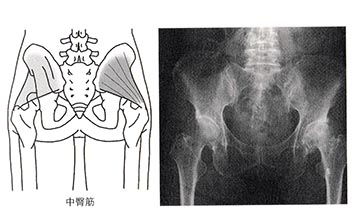

「初診時、左股関節痛のためひどい跛行がありました。階段の昇り降りにも手すりが必要でした。レントゲンで大腿骨骨頭に膿腫があり、関節裂隙の狭小化も認められました。左小臀筋、中臀筋にプラセンタのトリガーポイント注射(1回2アンプル/週1回)をおこないました」

「変形性股関節症は、生まれつきの股関節脱臼や外傷などが原因で股関節の関節が狭くなり、股関節痛を起こす病気です。ただし、40%は中臀筋、小臀筋の筋肉の硬結が原因になることもあります」

「股関節が変形しているからとすぐ手術することはなく、まずは中臀筋、小臀筋にプラセンタのトリガーポイント注射をし、それでも痛みが改善しなければ手術という選択も考えたほうが良いと思われます」